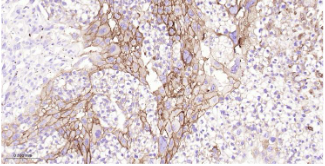

Immunohistochemical analysis of paraffin embedded Mouse placenta tissue slide using IHC0511M (Mouse ITGB3 Kit).